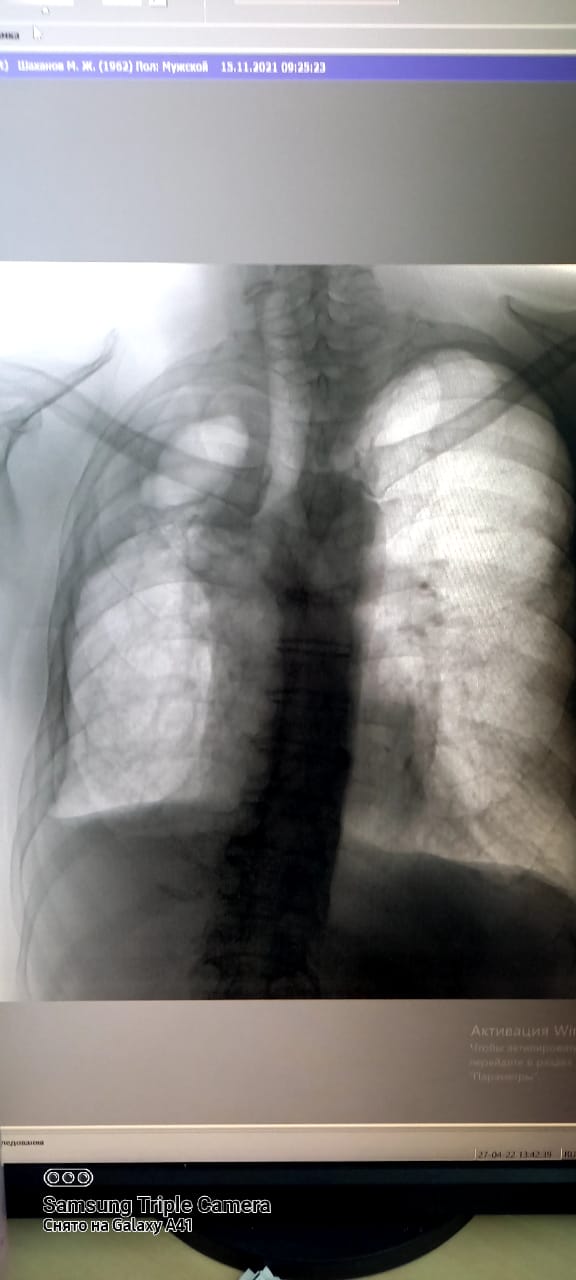

Туберкулез-инфекционное заболевание, возбудитель которого является Мycobacterium tuberculosis. Основной путь передачи туберкулезной инфекции-воздушно-капельный. Основным источником распространения инфекции являются больные туберкулезом легких. Передача заболевания происходит при вдыхании человеком зараженного микобактериями воздуха. Обычно заражение происходит в посещениях. Проветривание и хорошая вентиляция удаляют капельку из воздуха помещения, а прямые солнечные лучи быстро убивают микобактерии туберкулеза. Туберкулез излечим. Для выявления туберкулеза и других заболеваний используется в городской поликлинике №5 имеется новый флюорографический аппарат "ПРОСКАН-2000". Исследования проводятся с 15-летного возроста и старше, и по показаниям флюорография проводится 2 раза в год.